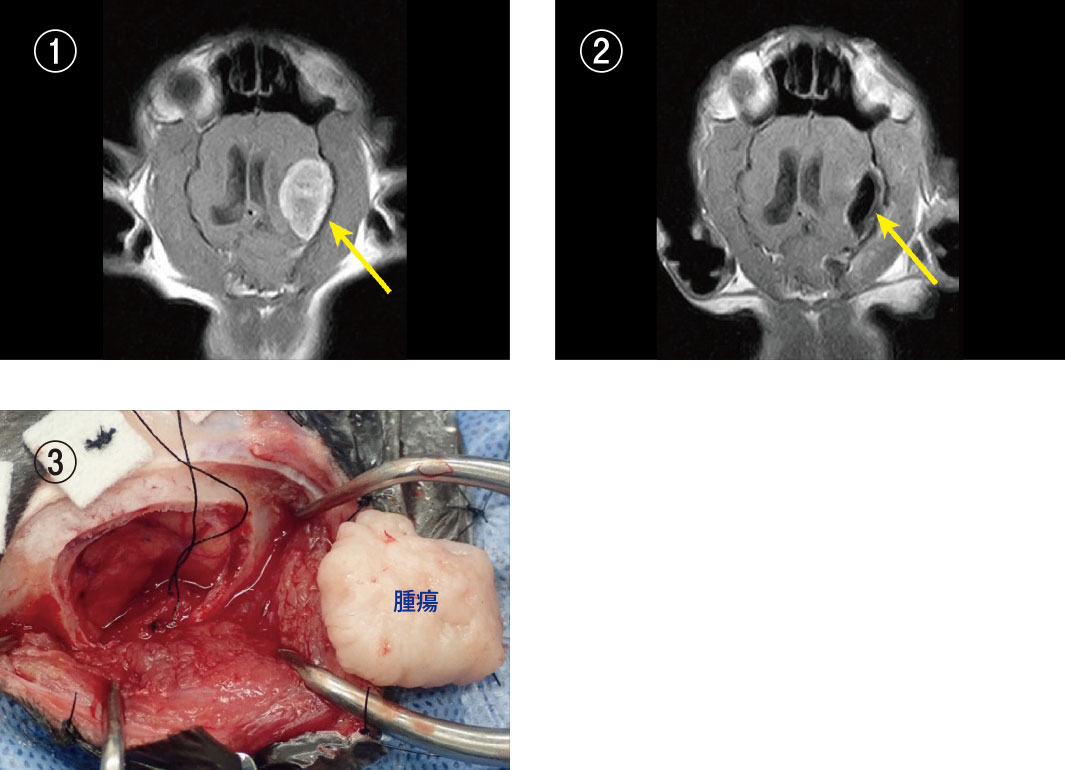

症例 ①犬、非定型髄膜腫(グレードⅡ)、後頭蓋窩に発生

① 手術用顕微鏡画像:腫瘍が大きくそのまま引っ張り出すことは難しいので、超音波乳化吸引装置を用いて腫瘍の内部をくり抜いて腫瘍を薄くしました。

② 手術用顕微鏡画像:周囲の小脳や延髄を傷害しないように、薄くなった腫瘍を慎重に引っ張りだしながら摘出しました。

③ 手術前MRI画像:後頭蓋窩に白く造影される大きな腫瘍が確認されました。

④ 手術後MRI画像:腫瘍が消失しました。術後9か月現在、再発はみられていません。